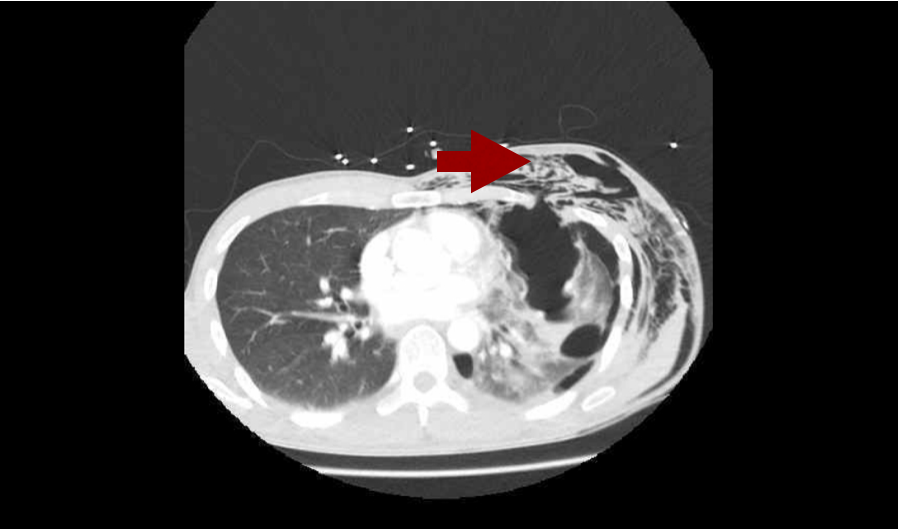

Pneumothorax is often associated with subcutaneous emphysema (free air in the tissues under the skin). It feels like bubble-wrap and looks like this on CT. Don’t press too hard though – it’s likely there are rib fractures underlying the air and they are extremely painful!